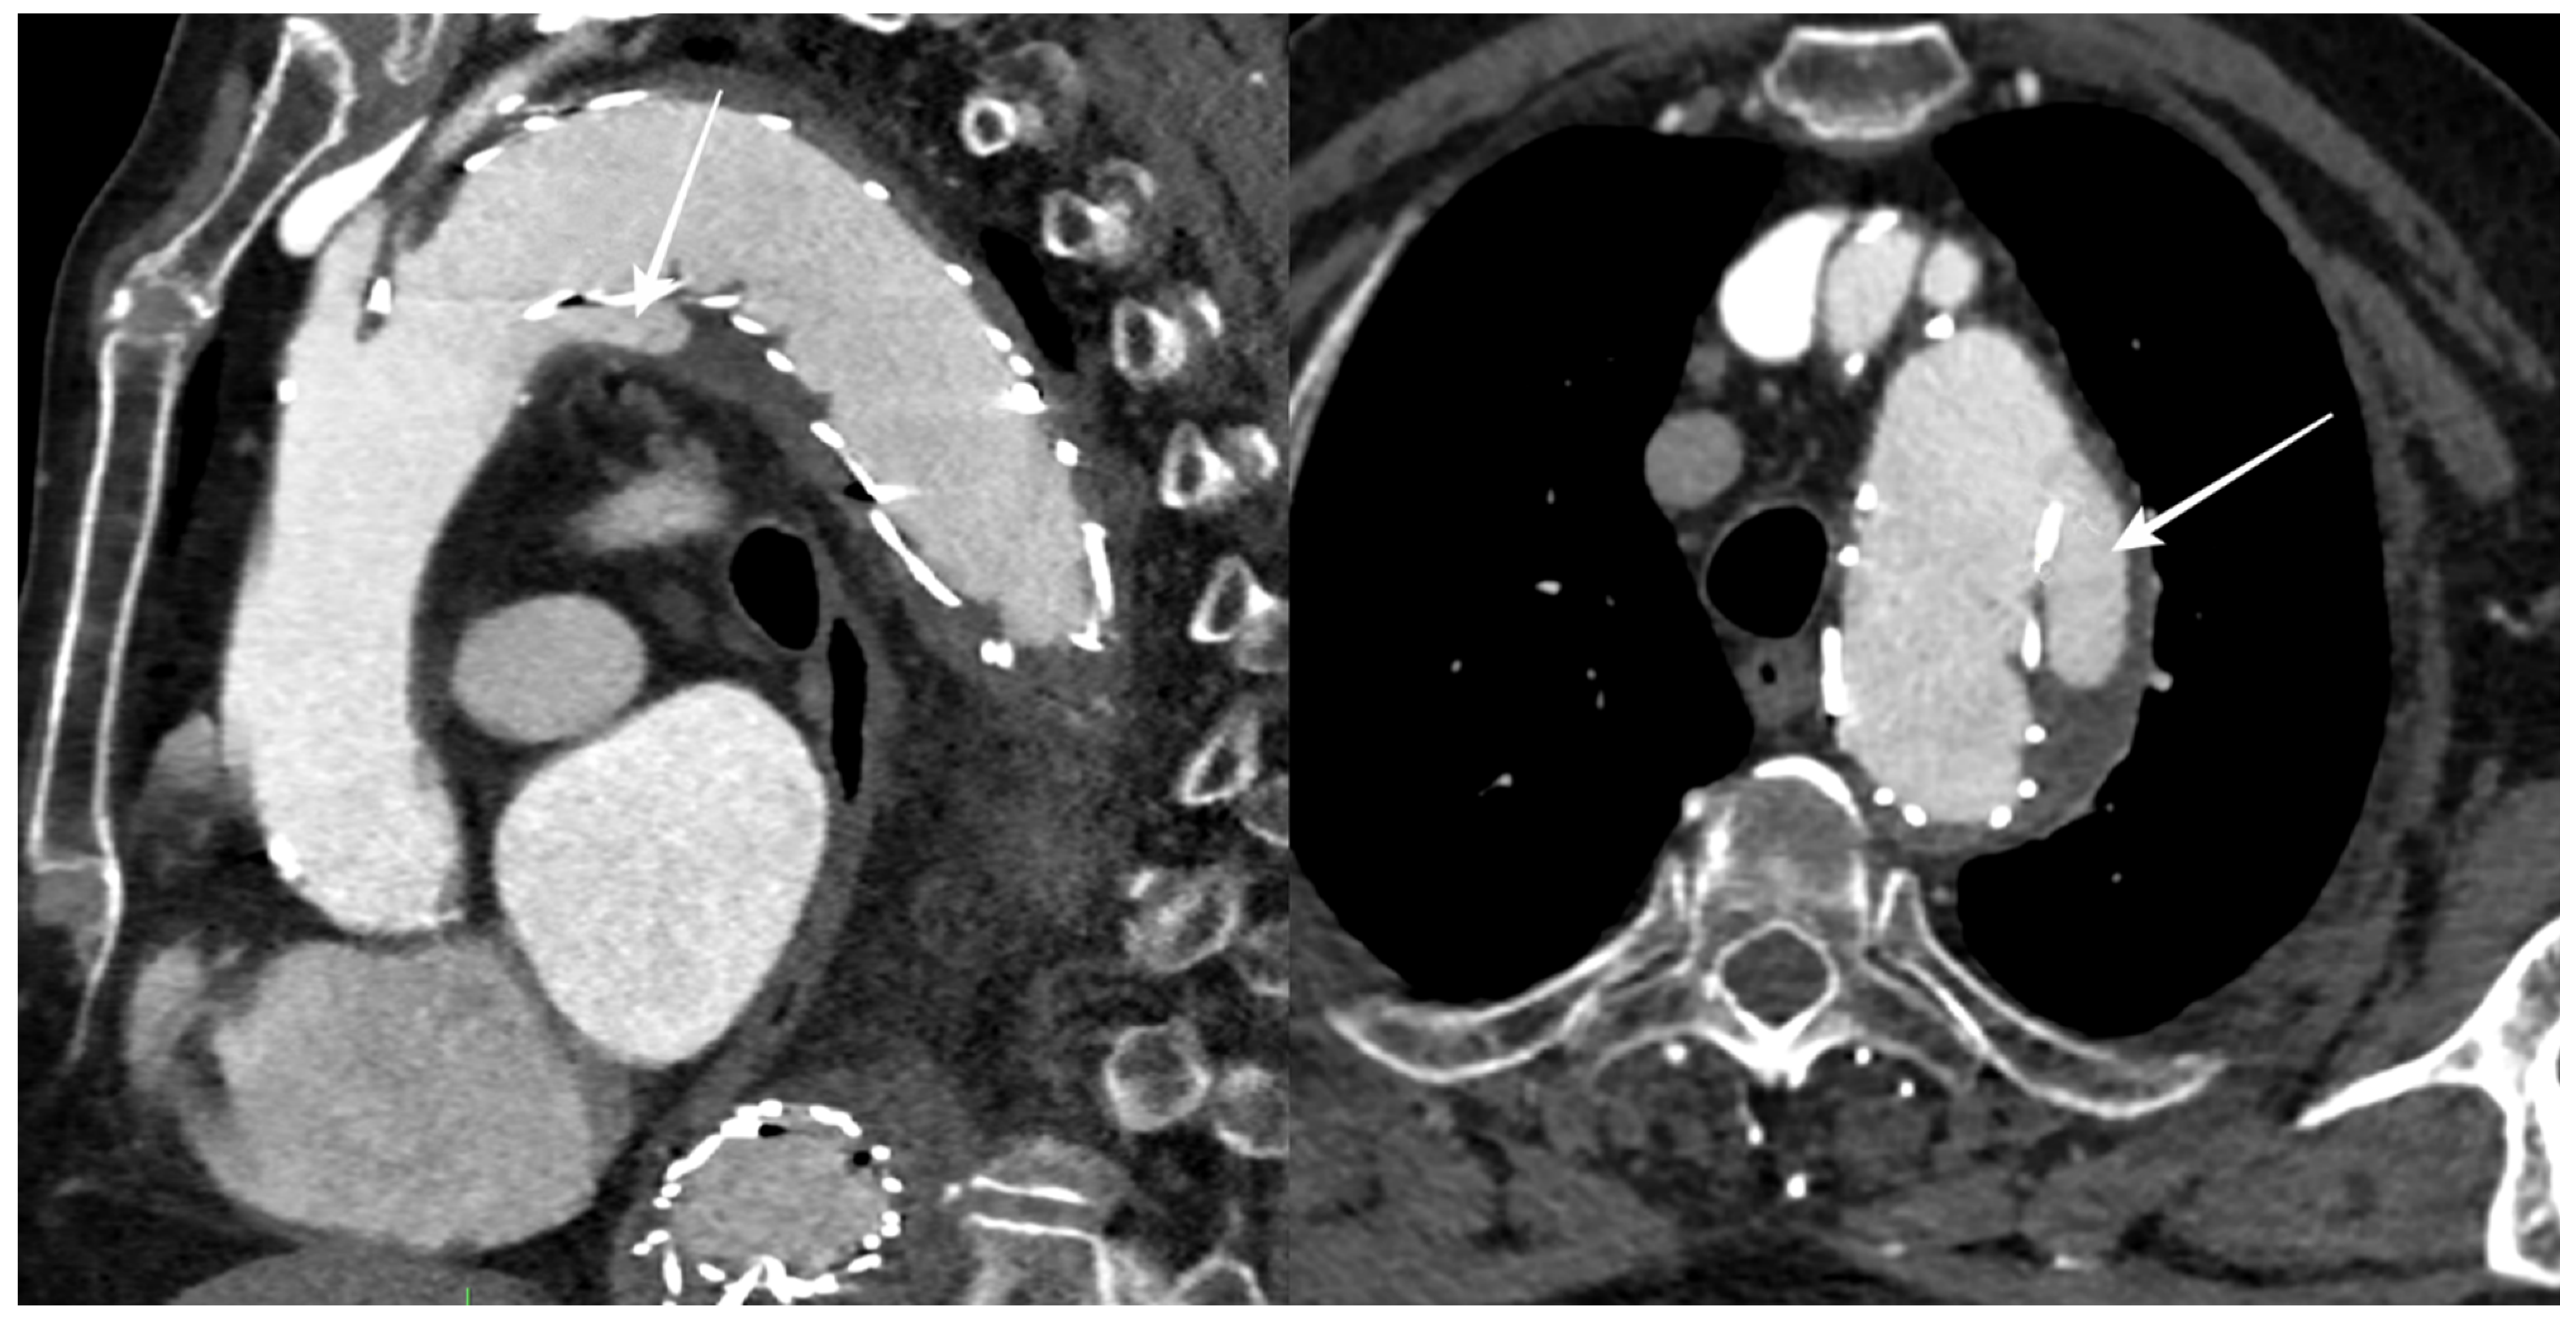

During the follow-up period, 12 patients (50%) had an endoleak, 5 of which were limited to a type II endoleak, while stent graft migration was reported in 6 patients (Figure 3).

Figure 3.

CTA follow-up after TEVAR for DTAA showing blood flow outside the stent graft at the proximal landing zone (arrows), with an incomplete seal of the DTAA (type Ia endoleak).